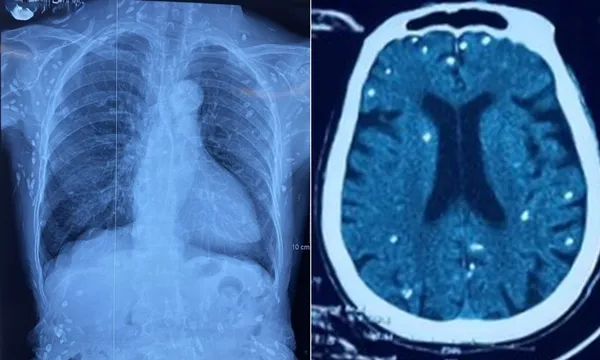

Nữ bệnh nhân (sinh năm 1948) được chuyển lên từ tuyến trước vì rối loạn ý thức đe dọa suy hô hấp, hình ảnh cắt lớp vi tính sọ não và X-quang ngực cho thấy rất nhiều nốt cản quang trong nhu mô não và dưới da vùng ngực-bụng.

Mặc dù xét nghiệm kháng thể IgM với sán dây heo âm tính, các tổn thương trên X-quang gợi ý bệnh nhân trước đây bị nhiễm ấu trùng sán dây heo, sau đó các nang sán trở nên vôi hóa và tồn tại lâu dài trong tổ chức.

Nang sán dây heo có thể tự thoái hóa hoặc bị vôi hóa, tạo nên nhiều hình ảnh cản quang phát hiện được trên phim X-quang như trường hợp bệnh nhân trên.